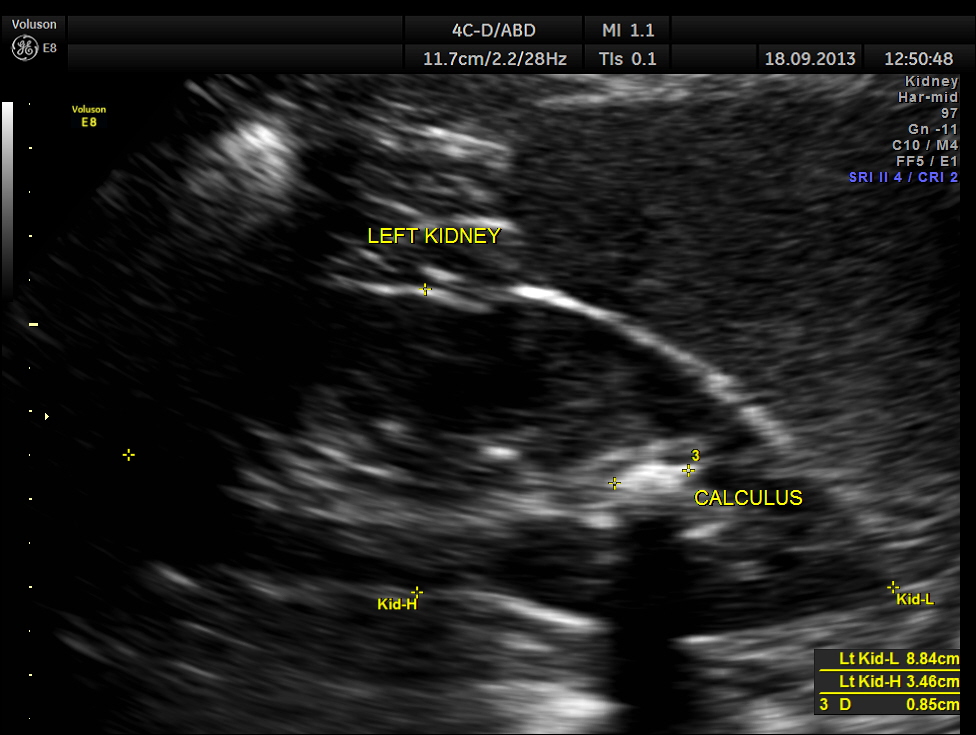

The left kidney showed a calculus.